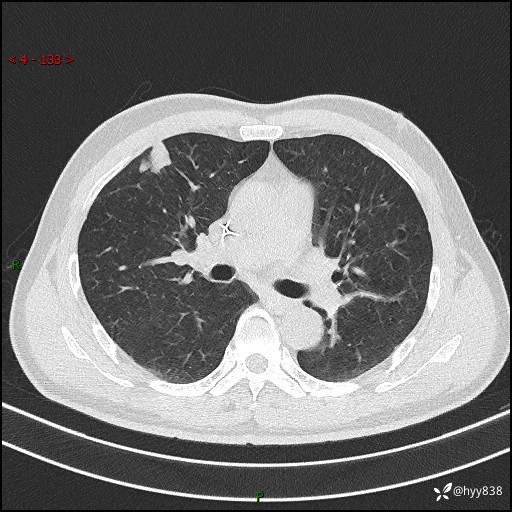

现病史:者10余天前因胸闷就诊于我院心血管内科,行胸部CT提示右肺上叶结节(24mm×16mm),考虑肿瘤性病变可能。无畏寒、发热、盗汗,无咳嗽咳痰,无咯血,无胸痛,无呼吸困难等不适,未予特殊处理。今为求进一步诊治,前来我院就诊,门诊以“肺结节待查”收住入院。 患者自起病来精神、食欲、睡眠尚可,体力下降,体重无明显变化。

胸部CT平扫+增强